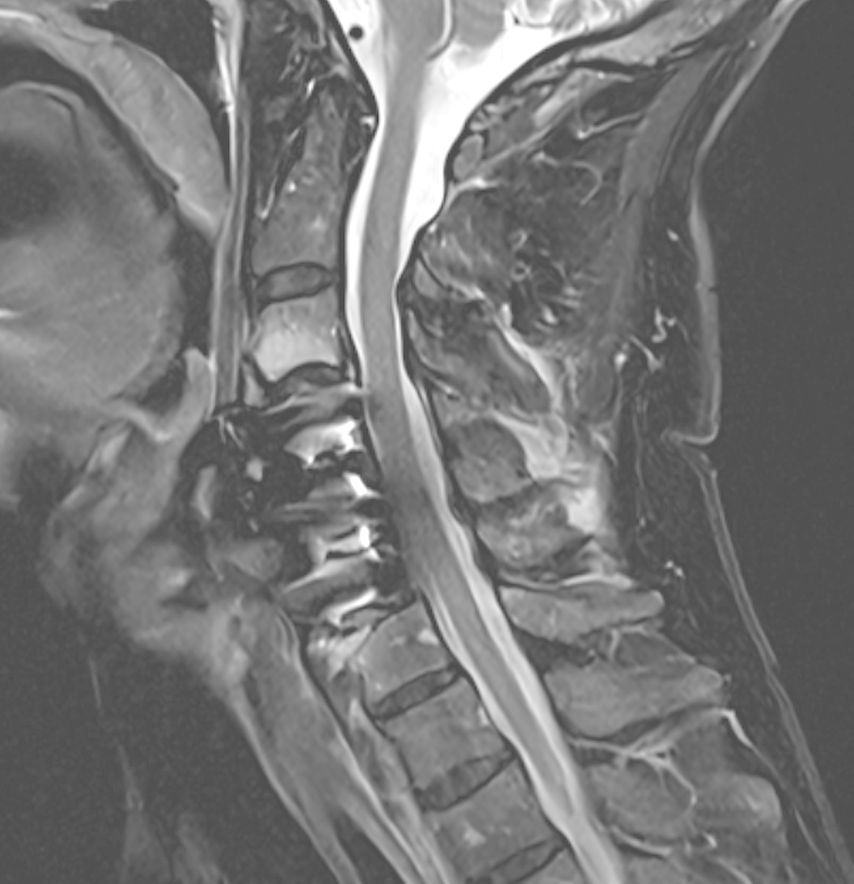

Intraoperative 3D-Visualisierung

Die Navigation stellt nicht nur beim Einbringen von Implantaten eine Hilfe dar, sondern kann auch in anatomisch herausfordernden Situationen rein zur Verbesserung der Orientierung zu Hilfe genommen werden. Mögliche Anwendungsfelder stellen hier beispielsweise die untere HWS oder der zervikothorakale Übergang dar, welche im konventionellen Röntgen teilweise schwer darstellbar sind. Abbildung 16 zeigt den MR-Befund einer 32-jährigen Patientin, die auswärtig zur ACDF C6/7 indiziert wurde, wobei der Eingriff dort aber aufgrund der Unmöglichkeit, die HWS unter Durchleuchtung entsprechend einzustellen, nicht erfolgte. Abbildung 17 zeigt das intraoperative Röntgen mit bereits kräftigem Schulterzug, in dem aber nur mehr das Segment C4/5 sicher beurteilt werden kann. In diesem Fall erfolgte mittels O-Arm der Eingriff navigiert. Ein anderes Beispiel ist die Anwendung zur Orientierung bei Osteotomien, wo die Navigation an unserer Klinik ebenfalls standardmäßig angewendet wird. Abbildung 18 zeigt einen intraoperativen Screenshot im Rahmen der Navigationsanwendung bei einer thorakalen Corporektomie (Th12) von dorsal im Rahmen einer Tumorresektion. Auch bei verkalkten Bandscheibenvorfällen, wie in Abbildung 19 dargestellt, kann die Navigation zur besseren intraoperativen Orientierung herangezogen werden. Ein weiteres Beispiel der vielfältigen Anwendungsmöglichkeiten der Navigation zeigt Abbildung 20. In diesem Fall wurde im Rahmen einer C1/2-Verschraubung nach Harms das Gelenk C1/2 beidseits navigiert zur besseren Fusion angefrischt.